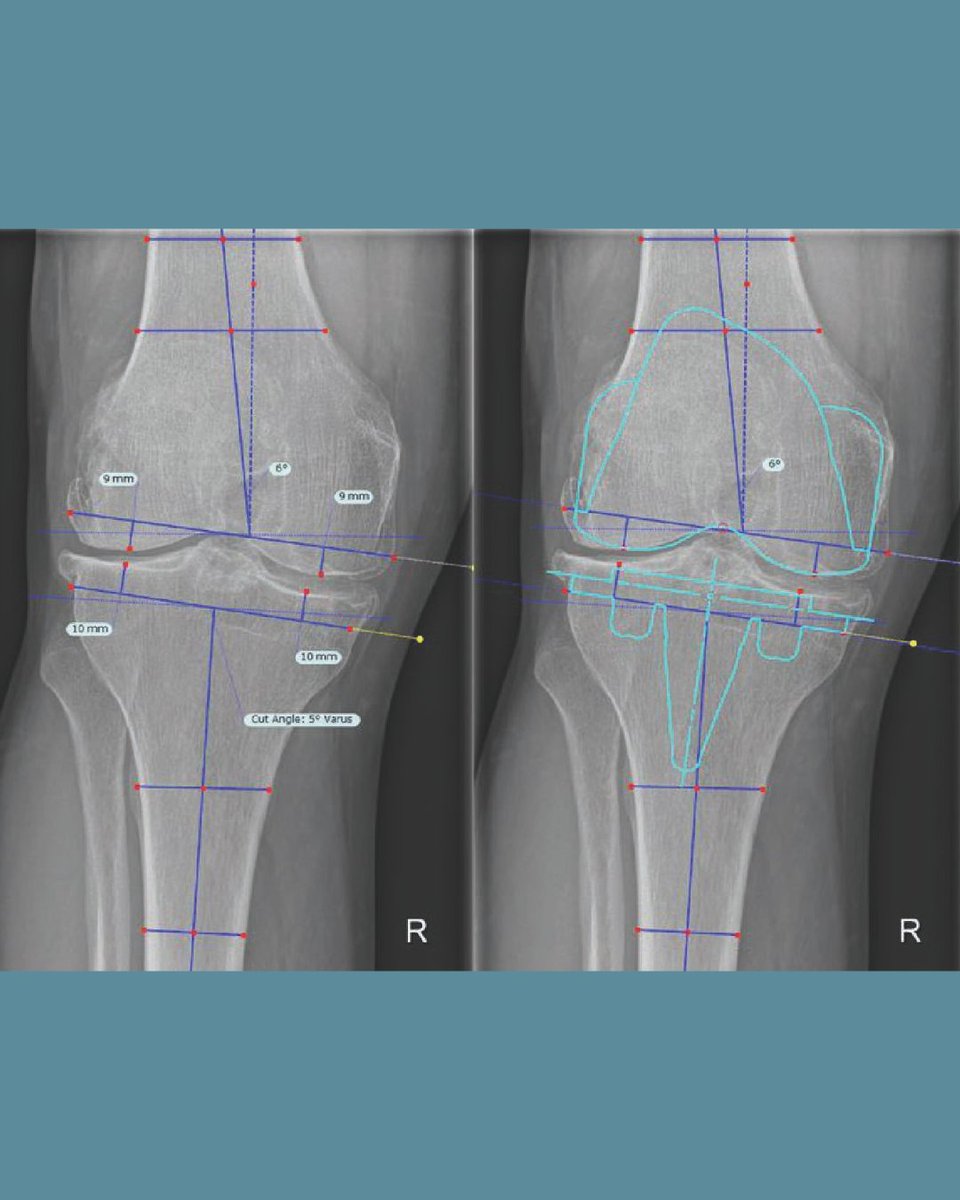

The future of total knee arthroplasty alignment involves balancing a traditional, robust mechanical alignment with personalized strategies informed by biomechanics and evidence.

#BJ360 #TKA #Arthroplasty #Biomechanics #Research